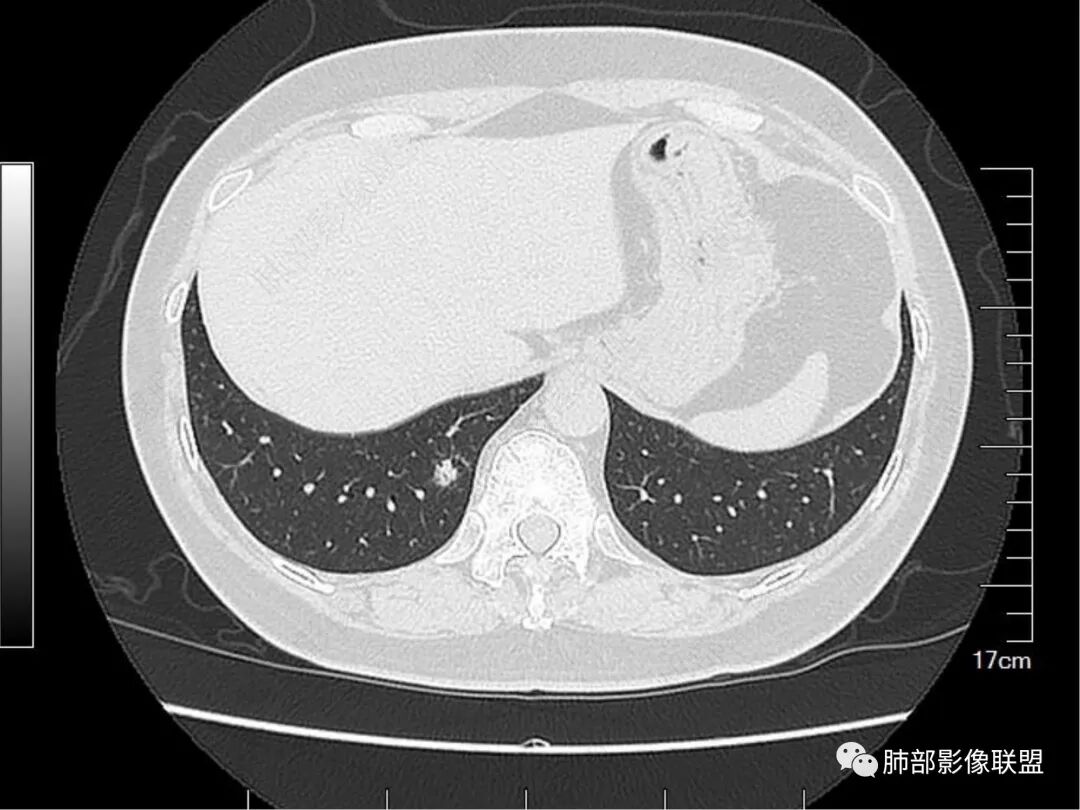

老年女性,右肺多发结节,形态不规则,有一定的收缩,内可见支气管影,周围可见边缘模糊的磨玻璃及长毛刺,考虑炎性病变,隐球菌感染可能。

老年人,右肺上叶后段小结节影,边缘清楚,血管进入,内可见支气管穿行扩张,周围晕征,边界清楚,胸膜牵拉,考虑腺癌。

考虑多中心腺癌

这个不敢拍死腺癌,也有可能是慢性炎,尤其是上叶病灶,找不到磨玻璃成分。

老年女性,右肺多发结节,形态不规则,有一定的收缩,内可见支气管影,周围可见边缘模糊的磨玻璃及长毛刺,考虑炎性病变。

右上肺膜玻璃影,边界清楚,临近胸膜牵拉,考虑腺癌,右下肺病灶考虑炎症。

MALT,鉴别多原发腺癌。

右肺上叶后段结节,考虑良性病变,肺泡腺瘤或者细支气管腺瘤可能,右肺下叶病变拍死炎性结节并局部纤维增生

右肺上叶后段及下叶后基底段混合磨玻璃结节,界不清,内似见扩张支气管,一年间有增大,考虑腺癌可能性,建议抗炎半月后复查

右肺上叶病变比较怪,不太像腺癌表现,下叶病变可以拍死炎性并纤维增生了

右肺上叶后段病灶考虑腺癌,右肺下叶后基底段病灶考虑粘液性腺癌,上叶病灶GGO清晰,收缩力强 下叶的病灶GGO模糊不清、收缩力弱

右肺上丶下叶病灶考虑同性质,混合磨玻璃结节,很多地方不太支持恶性(腺癌),比如扩张支气管可以在结节周边,以下叶的结节明显,磨玻璃边界欠清!综合考虑良性结节,支气管畸形结节可能!

就是没看到复查片总不踏实。这个结节的特点有些怪,连续的层面显示内部、边缘就是一张网格,走形非常自然,这些图,你看到的GGN边缘就不踏实,这是GGN边缘?还是就是增厚的间质

老年女性,体检发现、一年“稍增大”,右上肺结节(扩张小支气管或空泡+收缩力明显),考虑腺癌(腺泡为主),右下肺结节(边缘模糊GGO+扩张小支气管),考虑肉芽肿性炎(隐?),一元论:MALT不考虑(右上肺病灶收缩力太明显)

右肺上叶后段及下叶后基底段亚实性结节,边界清楚,不规则,支气管血管破坏,结节见小空泡感,老年女性,复查拟有所增大,支持恶性,IAC。

右肺多发磨玻璃结节,上叶结节可见分叶及空泡,结节内血管穿行,血管影粗细不均,结节内支气管扭曲,定性恶性,下叶者结节较散,边界不清,综合分析支持多原发微浸润性腺癌,实际工作中右上结节为主病灶,诊断恶性依据充足,右下病灶建议抗炎后复查更稳妥